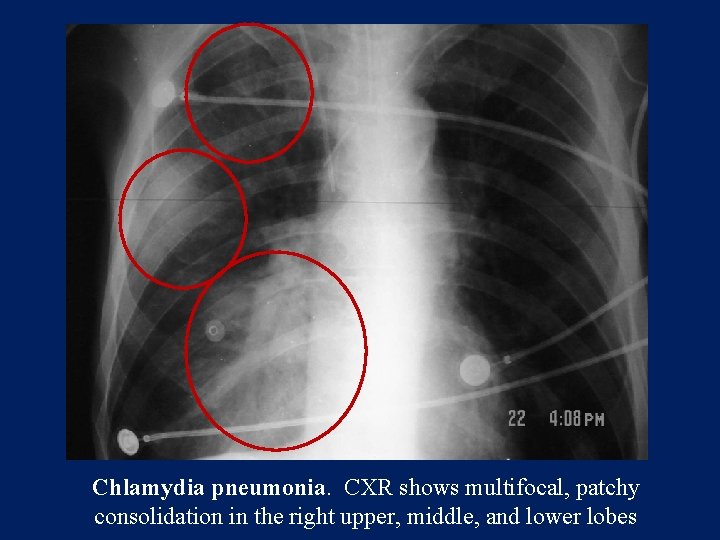

Radiology

Patchy reticular or reticulonodular opacities. Subsegmental and sometimes segmental atelectasis. Hilar adenopathy Pleural effusion

Chlamydia pneumonia. CXR shows multifocal, patchy consolidation in the right upper, middle, and lower lobes